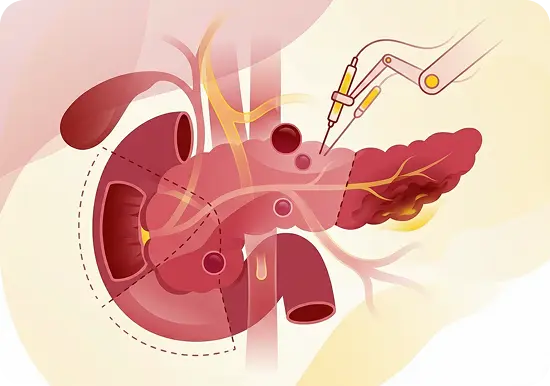

Pancreatic Surgery

- Whipple procedure (Pancreaticoduodenectomy)

- Distal and total pancreatectomy

- Minimally invasive and robotic-assisted pancreatic surgery

- Surgical management of pancreatic cysts and neuroendocrine tumour

- Vascular resections in pancreatic cancer surgery

- Surgical drainage of pancreatic pseudocysts

- Necrosectomy for infected pancreatic necrosis

- Surgery for chronic pancreatitis